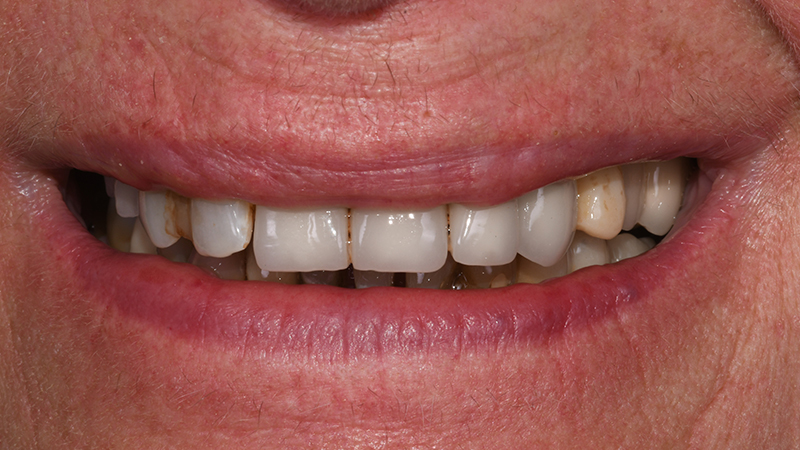

Ponendo vincoli relativamente alle tempistiche e richiedendo una riabilitazione protesica fissa, il piano di trattamento individuale è stato orientato verso riabilitazione protesica fissa a supporto impiantare a carico immediato per la sostituzione degli elementi 13-12-11-21-22-23-24 (Figs. 1, 2)

Sorriso in visione frontale extra-orale

Fig. 1 - Sorriso in visione frontale extra-orale